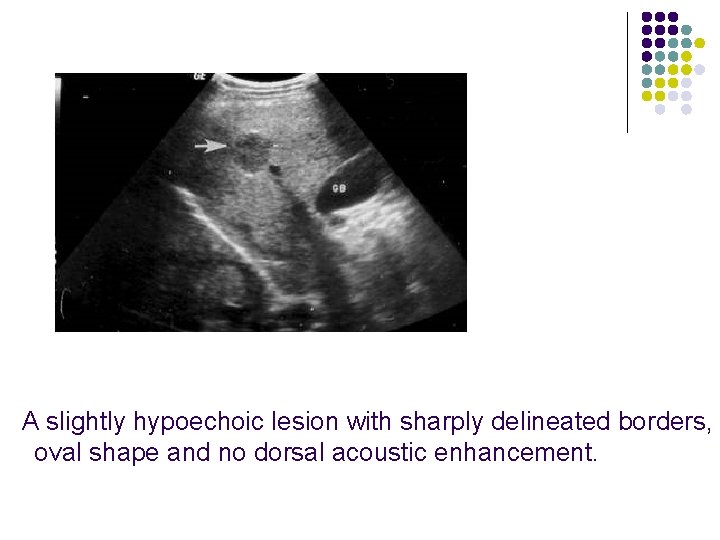

Ultrasonic features of Hepatic hemangioma l l l Uniformly hyperechoic mass(60 -70%) Inhomogeneous hypoechoic mass (up to 40%) Homogeneous(58 -73%) /heterogeneous May show acoustic enhancement(37 -77%) Unchanged in size/appearance(82)on 1 -to-6 year follow-up No Doppler signals/signals with peak velocity of <50 cm/cm

A slightly hypoechoic lesion with sharply delineated borders, oval shape and no dorsal acoustic enhancement.